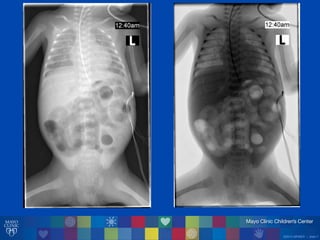

• Chụp XQăổăbụng

©2014 MFMER | slide-7

• Chụp X quang bụng

• “Khí ởătĩnh m ch c a ởătrong gan và khí ởătrong quai ru t non

ởăhố chậu phải và hố chậu trái”

• Chẩn đoán: Viêm Ru t Ho i T